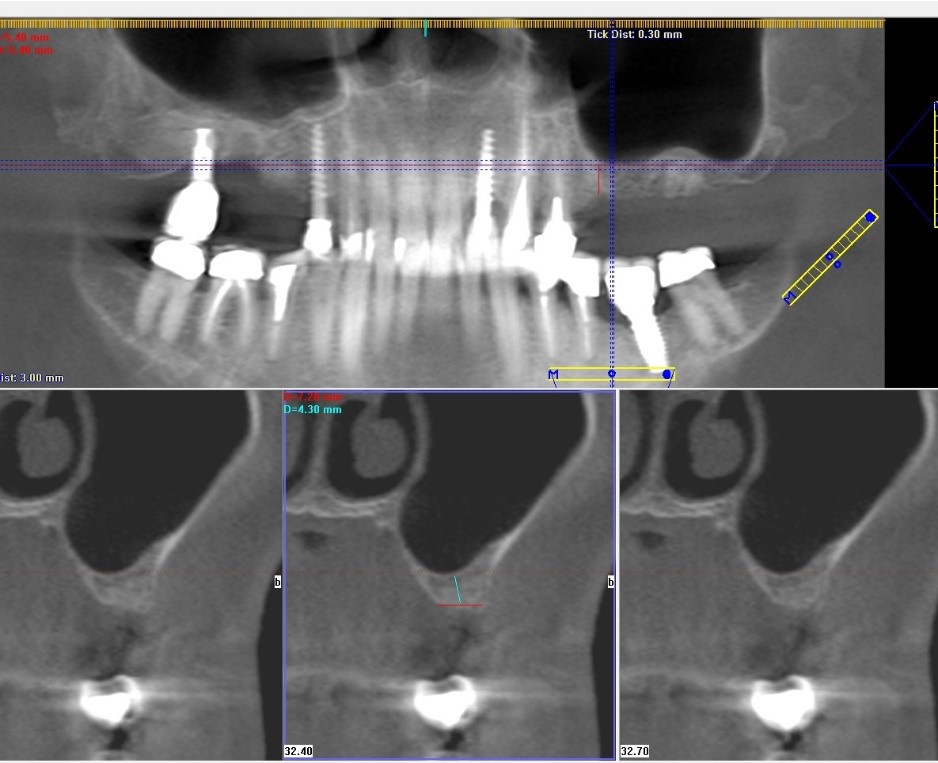

Au cours de la première visite un scanner 3D (CBCT - Cone Beam Computed Tomography) a été réalisé pour examiner l'état de l’os en 3 dimensions. Basé sur le scanner, nous avons déterminé que la hauteur et l’épaisseur ne sont pas suffisantes pour pourvoir poser des implants côté gauche, un remplacement osseux, notamment un sinus lift est devenu nécessaire. Du côté droit la zone des extractions n’est pas bien cicatrisée, un nettoyage chirurgical était nécessaire pour éliminer les tissus mous incarnés (tissu de granulation). L’implant 17, qui avait été précédemment posé dans une autre clinique, était également en très mauvais état, la résorption osseuse environnante et l'inflammation, la péri-implantite, justifiaient le retrait de l'ancien implant (explantation).

Le scanner, qui montrait la mâchoire supérieure et le sinus, nous permettait de mesurer la hauteur et la largeur de l'os en 3 dimensions. Dans les 3 plus petites images plus petites, il était clair qu’il n’y avait que 4,3 mm de hauteur qui n’était pas suffisant pour la pose d’un implant. C’est pourqoui, un remplacement osseux (sinus lift) était nécessaire. Si la hauteur de l'os est supérieure à 4 mm, le remplacement osseux peut être fait en même temps que la pose des implants.